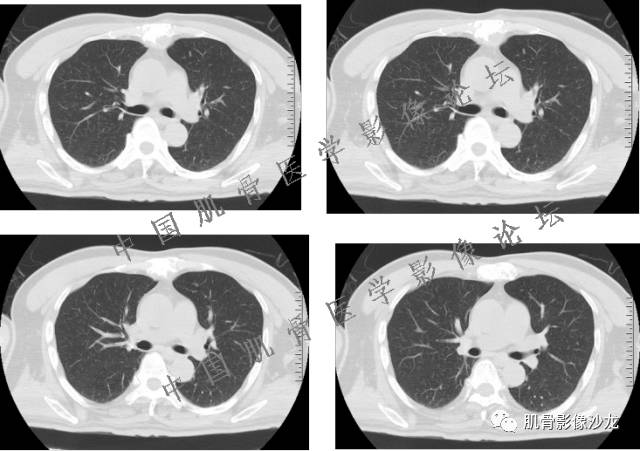

雪舞 :第二例,位于骶骨,有骨质破坏并有软组织肿块,软组织肿块边界清

雪舞: 第二例我们能够看到破坏与软组织肿块不成比例,软组织肿块大,破坏小

雪舞 :第二例挺难的,骨质破坏是溶骨性的,局部皮质中断,软组织肿块外缘光滑